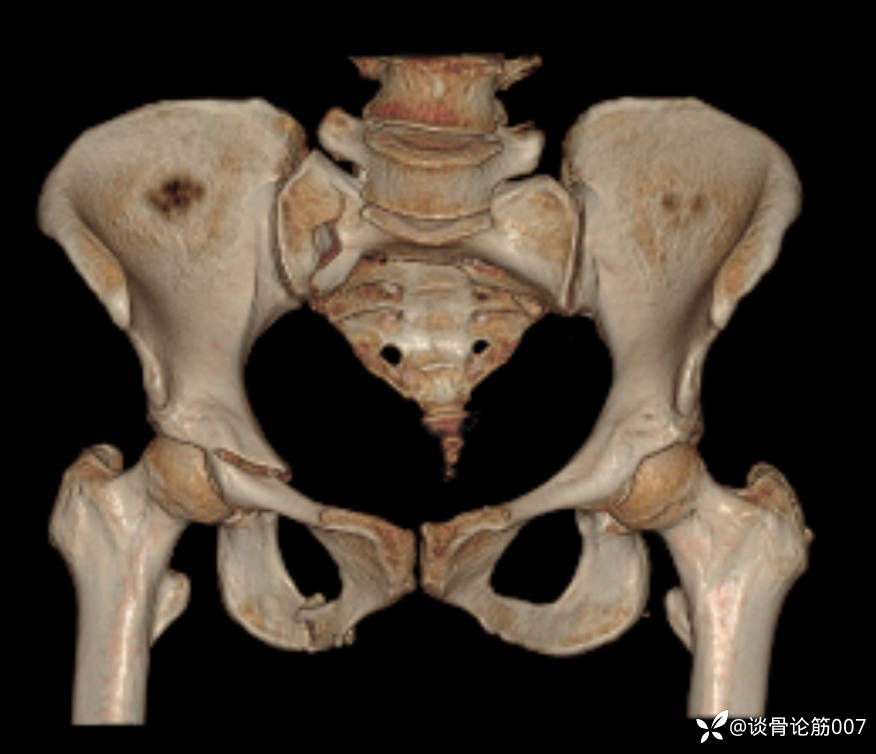

患者,女,50岁,“骑电动车摔伤后多处疼痛2小时。”为主诉入院。既往体健。入院查体面部肿胀严重,右侧腹股沟处疼痛,右髋屈伸时疼痛,骨盆挤压及分离试验阳性。DR:右侧耻骨上下支骨折,左侧耻骨上支可疑骨折。CT:骶骨骨折,右侧耻骨上下支骨折,左侧耻骨上支可疑骨折。面部多处骨折,右侧肩胛骨骨折。

骨盆B型骨折,给予闭合复位骶髂螺钉+耻骨上支螺钉固定。